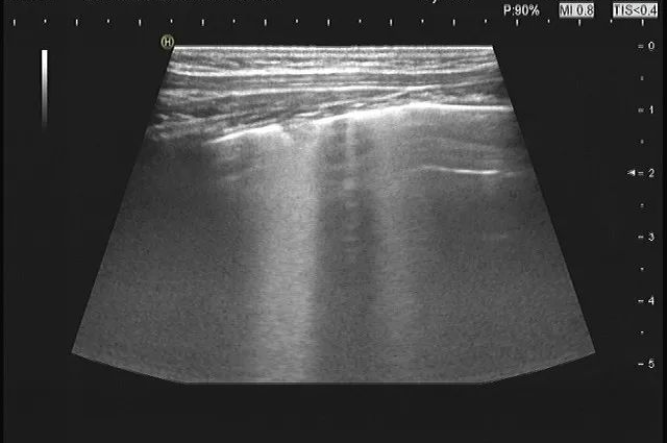

病例二:患兒4歲,咳嗽數(shù)日,超聲提示:右肺大片狀融合B線。